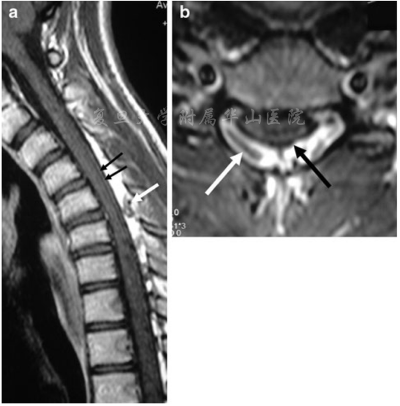

图2 屈颈位磁共振矢状和横断面T1相。(a,b)显示了造影剂给药后硬膜后壁的前移(黑色箭头)和扩大的硬膜囊后方空间。图像上可见血管流空影(白色箭头)

MRI(图2a,b)和CT血管造影显示屈颈时的硬膜外静脉丛明显扩张,术前进行了脑和颈部血管造影以排除血管分流(图3a-d)。屈颈时观察到静脉血从椎管外静脉流入椎管内静脉,硬膜后方静脉丛扩张。次日患者接受成功C4-C6及颈部硬膜成形术,硬膜固定至切除的椎板边缘。患者病情平稳,症状部分恢复(强度主观提高)。在为期12个月的随访中,患者的状况保持不变。